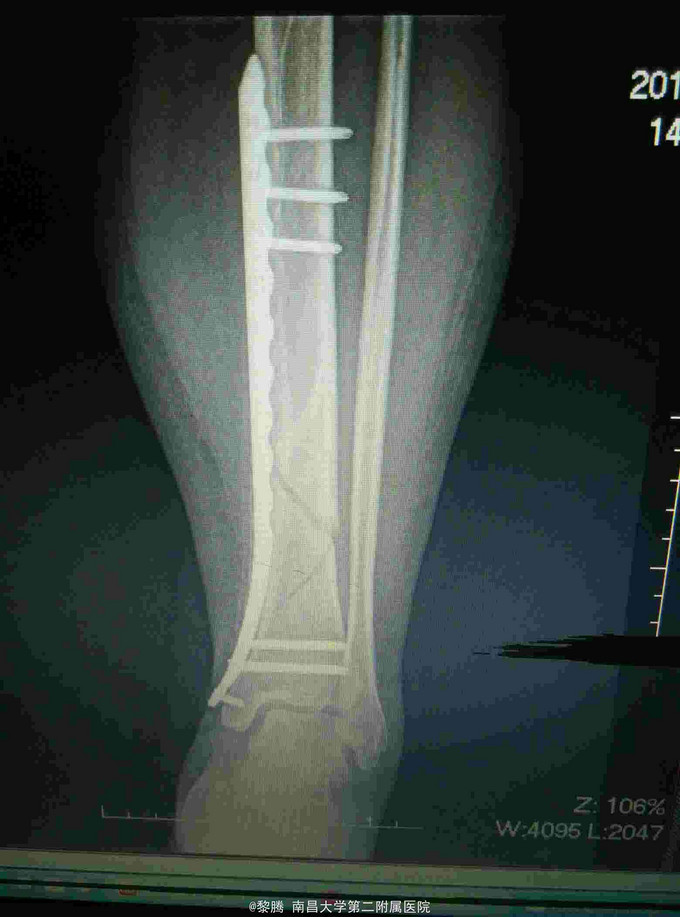

诊断:左胫腓骨骨折 治疗:胫骨骨折复位内固定

随访:术后3月患肢避免负重,定期复查。 讨论:患者行Mippo技术做骨折内固定,因行闭合复位,难以完全解剖复位,关键纠正旋转、成角,恢复正常力线。